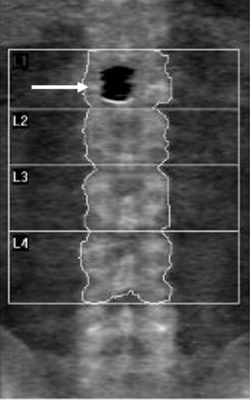

DXA imaging of the lumbar spine revealed a focal hypodense artifact over L1

Recent CT imaging showed hypodense artefact over L1 on DXA image as a platinum-containing stent placed for a gastroduodenal artery aneurysm at L1 level

The Z-score with L1 excluded is -2.6

The Z-score with L1 included is -3.3

Dual-energy X-ray absorptiometry (DXA) is the gold standard for measuring bone mineral density (BMD). While most exogenous materials (e.g., calcification, standard surgical hardware) present as hyperdense artifacts that falsely elevate BMD, certain high-density materials and lytic pathologies can manifest as “hypodense” artifacts (the “black hole” effect), leading to diagnostic challenges. A 47-year-old male with metastatic renal cell carcinoma (mRCC) on the tyrosine kinase inhibitor axitinib was referred for DXA following multiple atraumatic rib fractures. DXA imaging of the lumbar spine revealed a focal hypodense artifact over L1 (Fig 1A). Recent CT imaging for correlation identified this as a platinum-containing stent placed for a gastroduodenal artery aneurysm (Fig 1B). Consequently, L1 was excluded from the Z-score calculation to prevent inaccurate assessment. Additionally, a hypodense region was noted in the left proximal femur (Fig 2A), which matched a known lytic bone metastasis with cortical disruption previously seen on CT (Fig 2B). This case illustrates that high-atomic-number metals—such as platinum, tantalum, or lead—can paradoxicaly cause “black holes” on DXA because their extreme attenuation exceeds the software’s threshold for bone, causing it to incorrectly subtract the area as background or soft tissue. In this patient, the clinical picture was further complicated by lytic metastases from mRCC, which also produce focal hypodensity. Clinicians must maintain a high index of suspicion when encountering hypodense artifacts on DXA. Accurate interpretation requires correlation with anatomical imaging (such as radiographs, CT) and clinical history. Known causes of hypodense artifacts include lytic bone lesions, laminectomy sites, high-density metals (platinum, tantalum), and spina bifida.